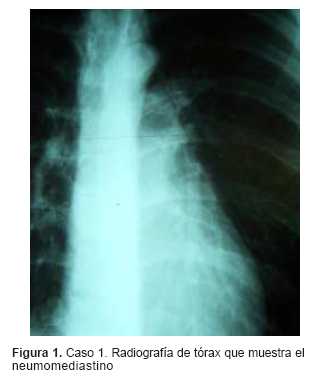

Se observa la existencia del neumomediatino en ambos estudios radiológicos de tórax (figuras1 y 2).

La tomografía axial computarizada (TAC) (figuras 3 y 4) confirma el neumomediastino y permite descartar otras lesiones asociadas, fundamentalmente la coexistencia de un neumotórax.

Radiológicamente en todos los casos se evidencia aire en el mediastino, que en el estudio de frente se observa como un halo radio lúcido contorneando la silueta cardíaca, así como la presencia de aire disecando las vainas peribroncovasculares. En un enfoque de perfil se puede visualizar mayor claridad en el espacio retroesternal.

La presencia de aire entre el pericardio y el diafragma es conocido como el signo del diafragma continuo.